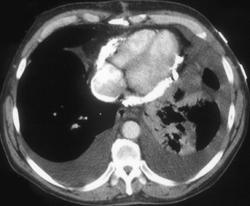

Bronchogenic Cyst